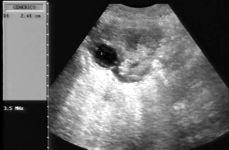

Data inserimento: 07 /11/2012Ecografia del: 31/10/2012 Strumento: Esaote MyLab 50 Gold - Responsabile Linea Cardio Esaote Regione Marche Dr. Franco Fabi Sonda: Convex Multifrequenza 2,5-5 Mhz ed Endocavitaria 5-8 Mhz Età Paziente: F 37 anni Motivazione dell'esame: ritardo mestruale. U.M. 25/09/2012. Commento all'esame: le immagini ed il video documentano il sacco gestazionale delle dimensioni di 10 mm, confermato con ecografia transvaginale (dimensioni di 9,5 x 10,6 mm), con evidenza del sacco vitellino, indice sicuro di gravidanza intra-uterina e corrisdpondente alla quinta settimana di gestazione (5 + 1). Beta-HCG = 13.302 mU/ml. Conclusioni: gravidanza alla quinta settimana di gestazione. Potete esprimere le vostre osservazioni e commenti sul BLOG. Presentazione: Dr. Massimo Dolciotti - Ancona Elaborazione digitale: Andrea Dini - Ancona